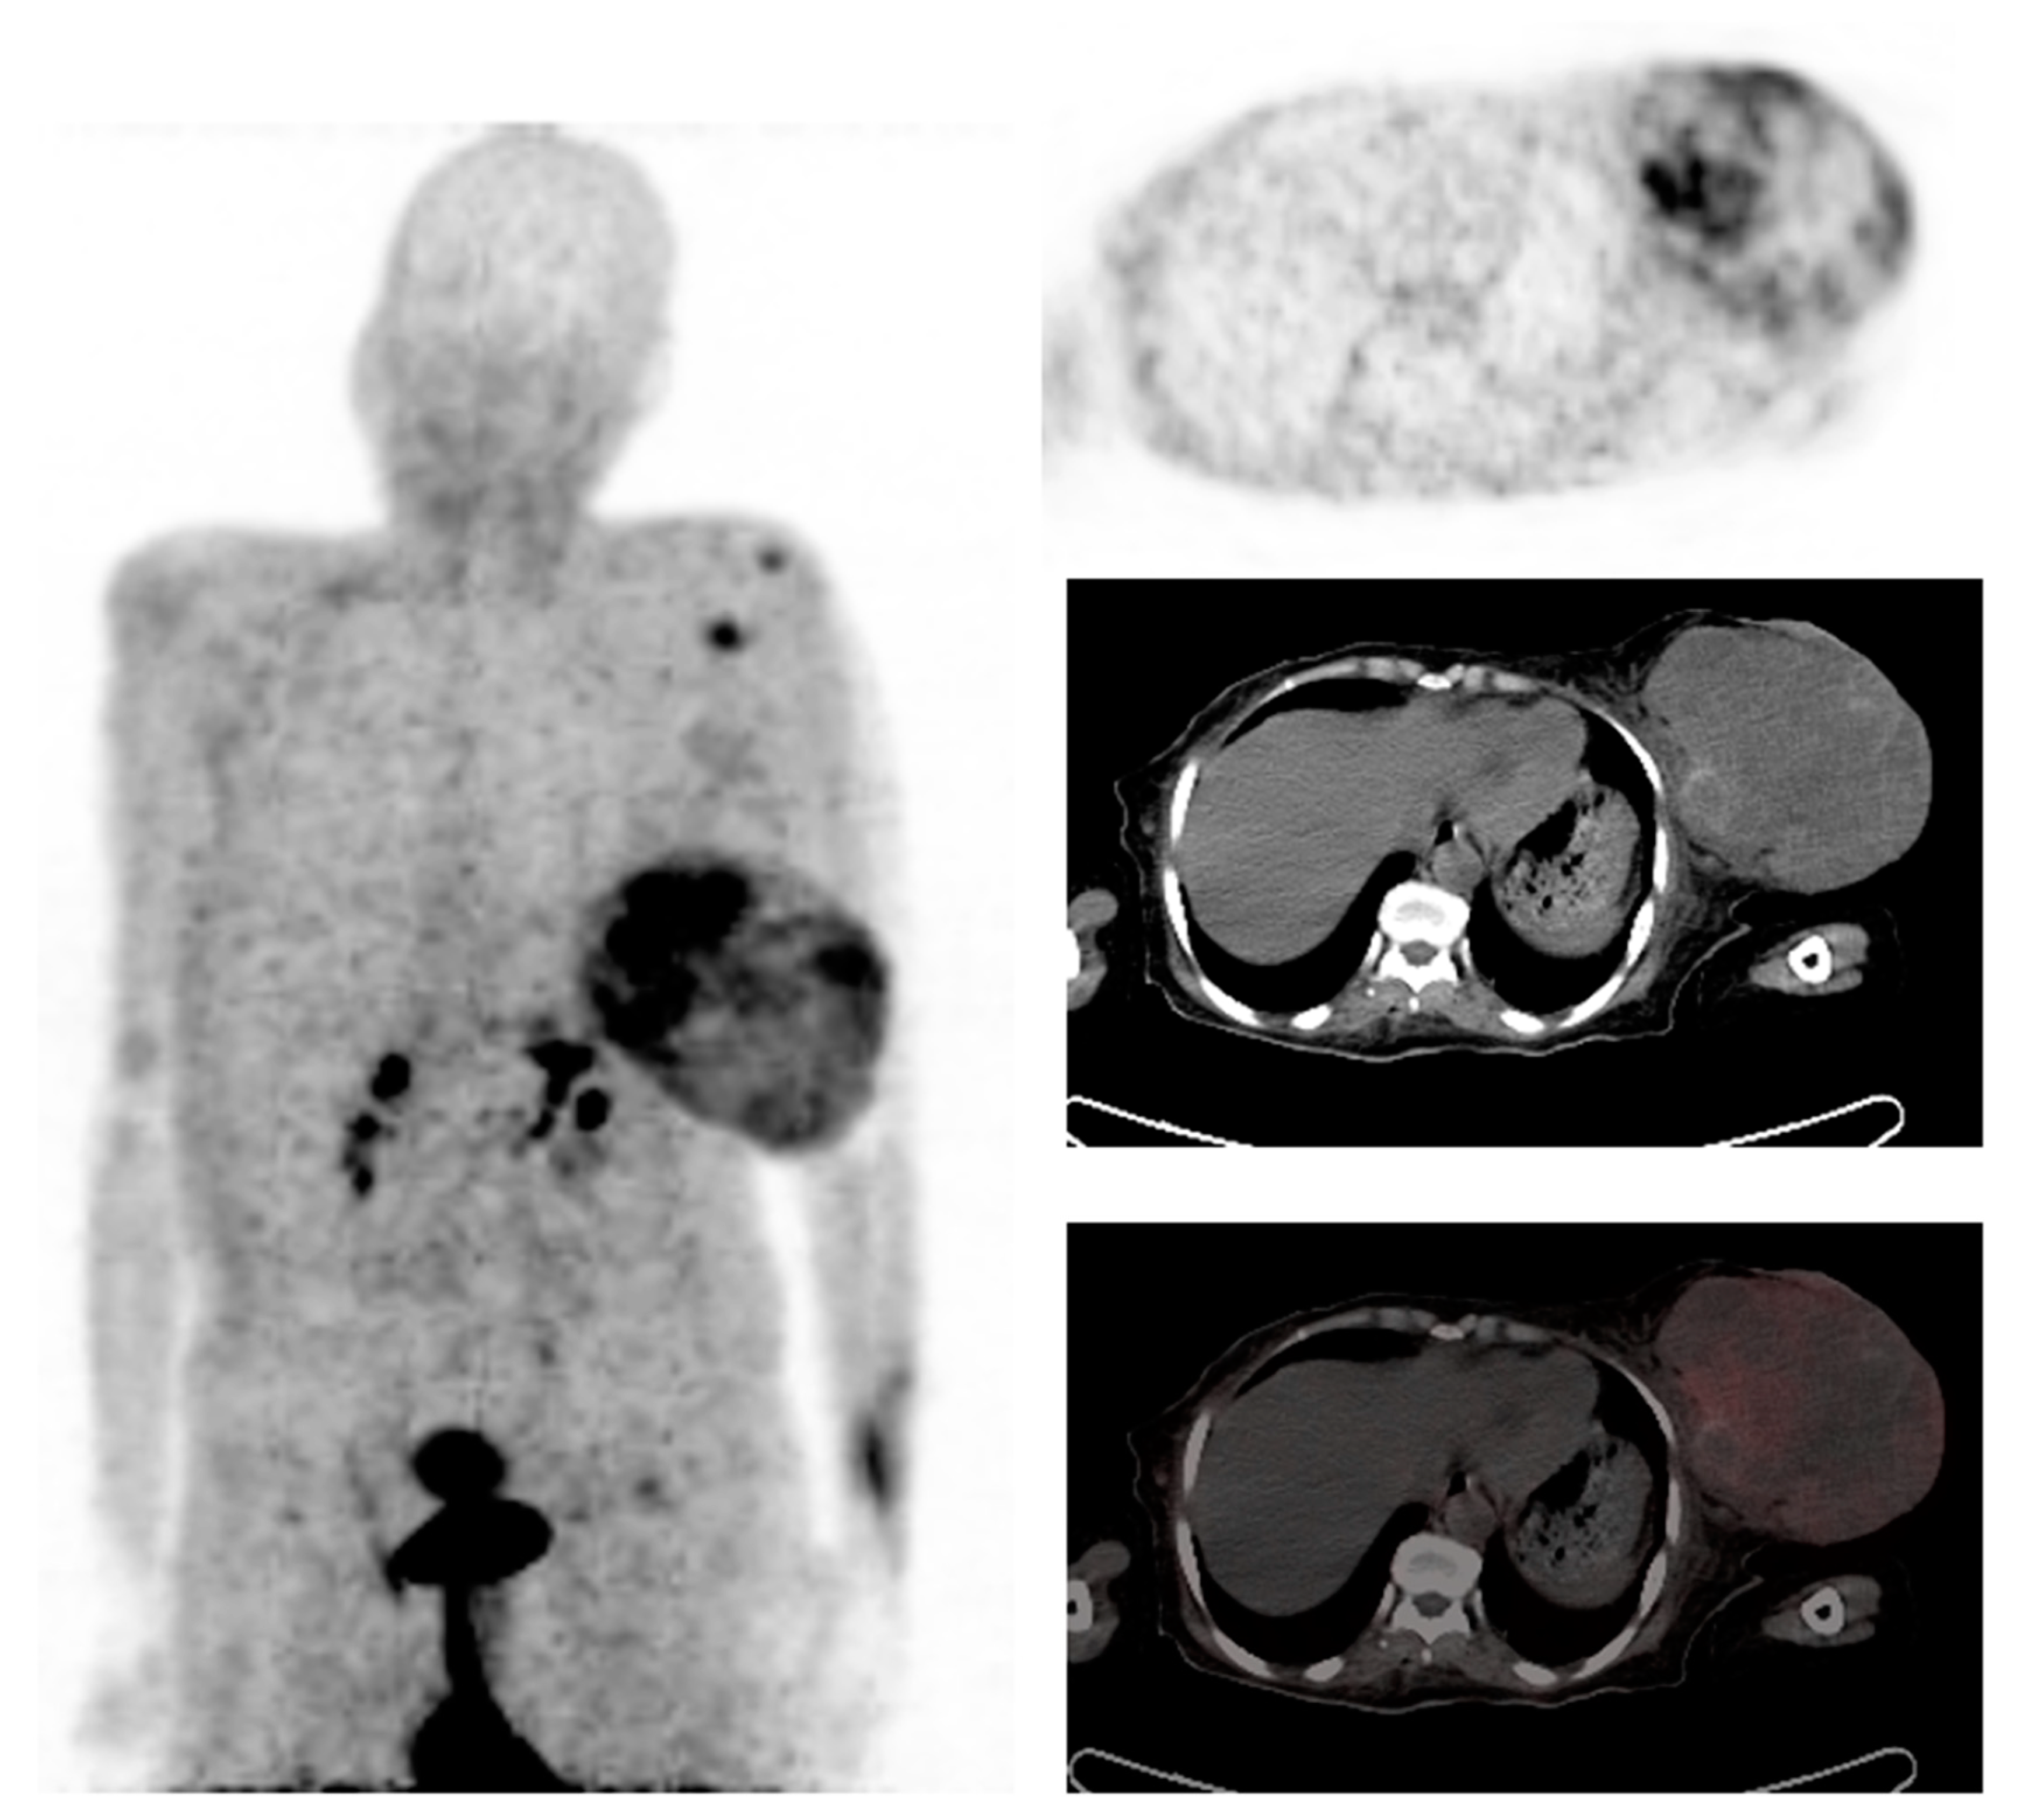

Prostate-specific membrane antigen (PSMA) is an integral membrane protein, mapped to chromosome 11q14, which is over-expressed by a high number of prostate carcinomas and has been reported to be overexpressed in the neovasculature of malignant tumors, including breast cancer, as demonstrated in Figure 3 [55]. In a study by Sathekge et al., 68Ga-PSMA-HBED-CC-PET/CT was evaluated in 19 breast cancer patients. A total of 81 lesions were identified, of which 84% were detected by 68Ga-PSMA-HBED-CC-PET/CT [56]. In total, seven patients underwent both 68Ga-PSMA-HBED-CC and 18FDG-PET/CT, with 18FDG-PET detecting 35 lesions and 68Ga-PSMAHBED- CC-PET detecting 30 lesions. It was noted that six of the 18FDG-positive lesions were negative on 68Ga-PSMA-HBED-CC-PET, while one of the 68Ga-PSMA-HBED-CC-positive lesions was negative on 18FDG-PET. In addition, Sathekge et al. suggested that there is a relationship between tumor metabolism as assessed by 18FDG uptake and tumor angiogenesis as assessed by 68Ga-PSMA-HBED-CC uptake [57]. Therefore, therapies targeting PSMA expression may be an option in patients with breast cancer who are refractory to standard therapies.

Figure 3.

A 39-year-old woman with stage IV breast cancer underwent 68Ga-PSMA PET/CT. The Maximum intensity projection PET demonstrated multiple osseous metastases and primary right breast cancer. Axial and sagittal fused PET/CT confirms the 68Ga-PSMA avid lesions in the right breast, sternum, and right iliac bone. Images reproduced with permission from [56]; published by Eur. J. Nucl. Med. Mol. Imaging, 2017.